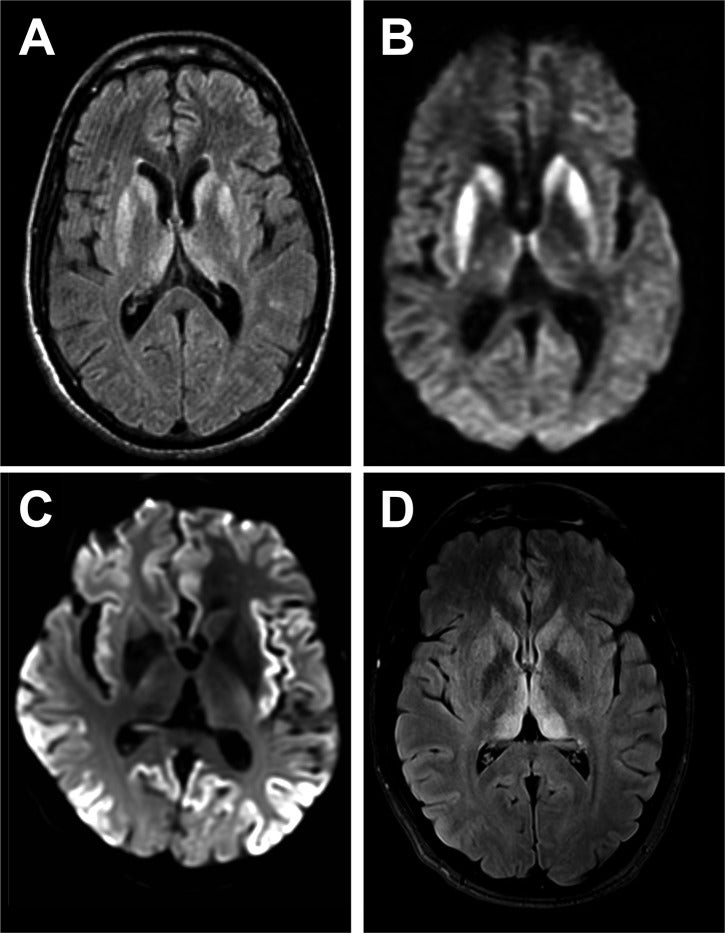

The rare and deadly disorder is caused by infectious proteins called prions, which can cause small holes in the brain that resemble sponges under a microscope.